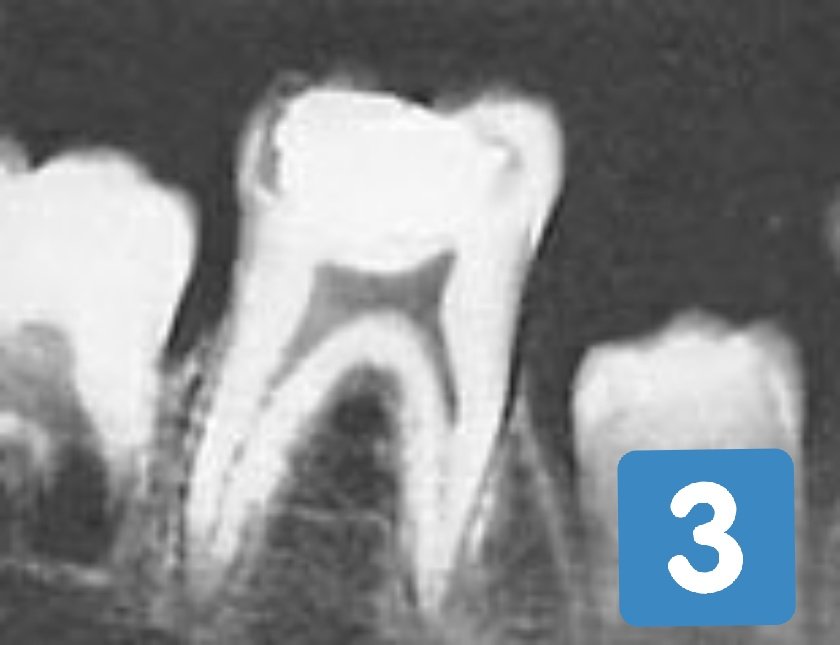

الأرقام أسفل توضّح الأجزاء الرئيسيّة للسن:

١ - الطبقة الطلائيّة.

٢ - الطبقة العاجيّة.

٣ - الغرفة اللُبِّية.

تبدأ المشاكل في الغالب، من تكوين متكرّر للصديد والتهابات وعدوى بكتيريّة وآلام مستوجبة لإزالة أعصاب عند تمكّن النخور من الوصول للغرفة اللُبِّية وتعريضها للمحيط الخارجي.

الأشعّة السينيّة للأسنان في الصور ٢،١ و٣ أسفل هي لثلاثة أطفال من مناطق مختلفة، عاشوا تحت بيئة غذائية متجانسة سيّئة، من محاصيل وزيوت نباتيّة، طحين وموارد مستوردة مع حد الأطعمة الحيوانيّة.

النخر من سوس الأسنان تمكَّن من الطبقة الطلائيّة والعاجيّة للسن ليبدأ كشف الغرفة اللُبِّية.

بعد رصد المحقّق للثلاث حالات، وقبل أي إجراء جراحي لأسنان الأطفال الثلاثة، هدَف برايس إلى معرفة أثر التغذية في هذه المرحلة المهمّة من حياة السن.

أخضع المحقّق الأطفال لبرنامج غذائي تُسجّل فيه تفاصيل التحليل الكيميائي للّعاب مع مكان وحجم وعمق النخر، لفترة زمنية قصيرة من أربعة أشهر.

البرنامج الغذائي المرسوم من المحقّق للثلاثة أطفال ارتكز على تغذية حيوانيّة شبه خالصة، متينة بمصادر الفيتامينات والمعادن والأحماض.

المتابعة الأسبوعية من المحقّق للثلاث أسنان أثناء البرنامج الغذائي الخاص للأطفال، تقصَّت إبداع الخَلْق الإلاهي وكماله، في قدرة أنسجة الغرفة اللُبِّية من إنشاء طبقة جديدة ثانويّة عاجيّة، حالت دون كشف الطبقة اللُبِّية من النخور للمحيط الخارجي، لتُجهض بذلك داعي جراحة معالجة الأعصاب!

تتابعت المفاجآت لبرايس عند تدوين التحسّن اللحظي بعد دخول البرنامج لمركّبات، معادن وإنزيمات اللّعاب من التحليل الكيميائي الدوري.

بعد أن كان التحليل الكيميائي للعاب يرمي إلى عامل أمان ضعيف جدًا، محفِّز لتنشيط سوس السن للنخر، أصبح العامل قوي جدًا ومستحكَم، معيق لاستمراريّة التسوّس.